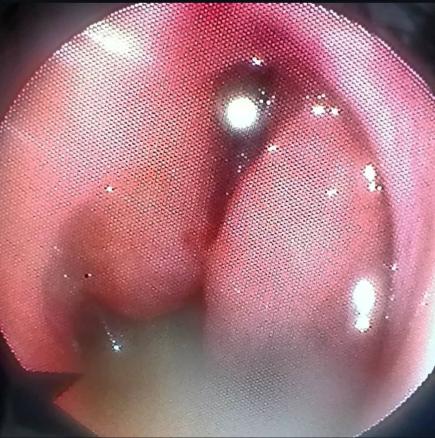

Une patiente âgée de 40 ans est admise à l’hôpital pour exploration d’adénopathies cervicales. L’interrogatoire révèle une obstruction nasale chronique accompagnée d’une rhinorrhée. L’endoscopie met en évidence une rhinite croûteuse avec un bombement du cavum (fig. 1). La tomodensitométrie montre un cavum pseudotumoral (fig. 2, 3 et 4). L’histologie objective un processus granulomateux tuberculoïde (fig. 5). Le GeneXpert sur fragment de biopsie, l’intradermoréaction à la tuberculine et la recherche de bacille de Koch dans les crachats sont négatifs.

La calcémie, la protéine C-réactive (CRP), l’angiotensine convertase et le bilan immunologique sont normaux. La confrontation des données cliniques, radiologiques, histologiques et biologiques retient le diagnostic de sarcoïdose. L’évolution a été favorable sous corticothérapie systémique.